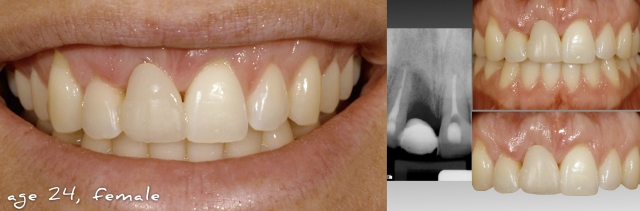

The following female patient lost her right central due to trauma and was treated at the age of 24 with a single tooth implant in the #8 site and veneers on teeth #’s 7, 9, 10 (See Fig.1). The definitive result shows nice symmetry in both the incisal edge positions and gingival margins of the central incisors (See Fig.2). At the 6-year follow up, a discrepancy can be seen in the incisal edge positions of the centrals (See Fig 3) The incisal edge discrepancy is significantly greater at 12 years (See Fig. 4). To what can we attribute this change? Is it due to eruption of the anterior teeth due to unstable occlusal contacts? Or is it due to eruption of the teeth due to continued facial growth?